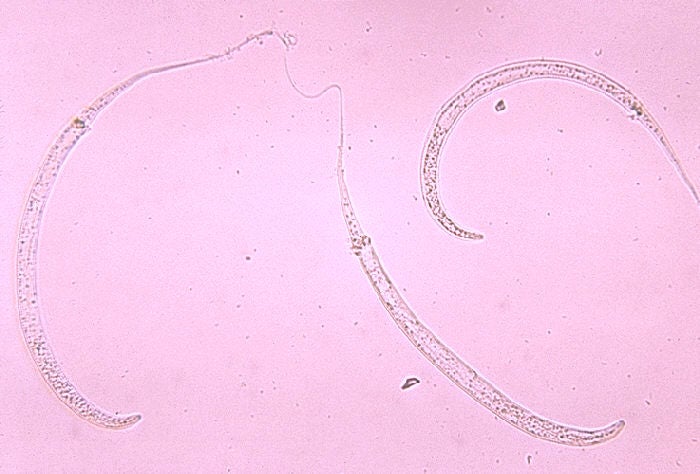

Guinea worm, formally called Dracunculus medinensis, is a type of nematode that’s long been a thorn in our sides, likely having been documented as far back as Biblical times. Its complicated life cycle starts out in freshwater, when larvae are eaten by tiny crustaceans known as copepods. When we unknowingly ingest these copepods through drinking water (or eating undercooked fish that ate the copepods), the worms burst free and reach our intestines, where they fully mature and mate. The males then die and the pregnant females migrate to a spot underneath our skin, usually along our legs. About a year post-infection, the females cause a blister to form. And when this blister breaks, the worm slowly begins to emerge from our skin, triggering a painful burning sensation that drives the infected to cool their wound off in the nearest water source. Once this happens, the worm releases thousands of larvae into the water, starting the whole thing again.